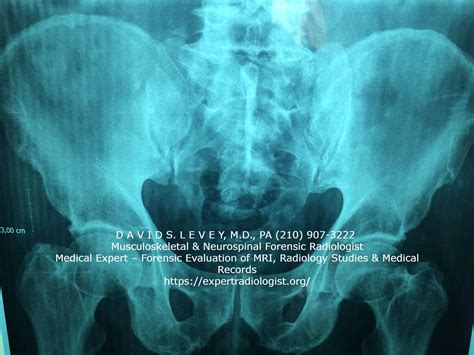

Hey guys, let’s dive into the world of medical imaging and explore what makes a Nelson Radiologist such a crucial part of healthcare. When we talk about Nelson Radiologist , we’re really talking about highly trained medical professionals who specialize in interpreting medical images like X-rays, CT scans, MRIs, and ultrasounds. These images are like a secret code that helps doctors diagnose diseases, monitor treatment progress, and even guide minimally invasive procedures. The accuracy and insight provided by a skilled radiologist can quite literally be the difference between life and death, or at least a significant impact on the quality of life for a patient. Think about it: a subtle shadow on an X-ray, a tiny anomaly on an MRI – these are the things that a radiologist, with their trained eyes and deep understanding of anatomy and pathology, can spot when others might miss them. They are the detectives of the medical world, piecing together clues from these visual representations to paint a clear picture for the patient’s treating physician. The field of radiology itself is constantly evolving, with new technologies and techniques emerging all the time. This means that a Nelson Radiologist isn’t just looking at static images; they are often working with cutting-edge equipment that provides incredibly detailed views of the human body. This allows for earlier and more accurate diagnoses, which in turn leads to more effective treatment plans. It’s a demanding field, requiring years of rigorous education and continuous learning to stay at the forefront of medical advancements. We’re talking about medical school, followed by a demanding residency program in radiology, and often further subspecialty fellowship training. This dedication ensures that when you need a radiologist, you’re getting someone with unparalleled expertise in their field. The role of a radiologist extends beyond just reading scans; they often collaborate closely with other physicians, discussing complex cases and offering their expert opinions to ensure the best possible patient care. They are integral members of the healthcare team, contributing vital information that guides surgical decisions, chemotherapy regimens, and follow-up care. Their work is often behind the scenes, but its impact is profound, touching the lives of countless individuals every single day. Understanding the importance of a Nelson Radiologist means appreciating the intricate science and dedicated skill involved in medical imaging and diagnosis.

When it comes to getting to the bottom of what’s ailing you, the expertise of a Nelson Radiologist is absolutely paramount. Guys, imagine you’ve had a scan – maybe it’s an MRI for a knee injury or a CT scan to check for something more serious. That scan generates a ton of data, a complex series of images that require a special kind of vision to interpret. This is where our Nelson Radiologist shines. They possess a unique understanding of human anatomy, physiology, and the myriad ways diseases can manifest visually within the body. It’s not just about seeing something; it’s about understanding what that ‘something’ means in the context of your symptoms and medical history. They can differentiate between a normal anatomical variation and a sign of pathology, which is a huge deal. For instance, a radiologist might identify a small nodule on a lung CT scan. While it might seem insignificant to the untrained eye, a radiologist will assess its size, shape, density, and location, comparing it to previous scans if available, to determine if it’s something to be concerned about – perhaps an early sign of cancer that requires further investigation. This Nelson Radiologist is essentially the translator between the complex visual language of medical imaging and the practical needs of diagnosis and treatment. They write detailed reports that explain their findings in clear, concise terms, allowing your primary care physician or specialist to make informed decisions. Without this critical interpretation, those scans would just be a collection of pictures, offering little diagnostic value. Think about the sheer volume of information a radiologist processes. They often review hundreds of images a day, each requiring careful attention and critical analysis. This level of dedication and precision is what makes their contribution so invaluable. Furthermore, radiologists are not just passive interpreters. Many are involved in interventional radiology, a subspecialty where they use imaging guidance to perform minimally invasive procedures. This could involve draining an abscess, placing a stent, or performing a biopsy – all while using real-time imaging to navigate the body with incredible accuracy. So, when you hear about a Nelson Radiologist , understand that you’re talking about a cornerstone of modern medical diagnostics, a professional whose keen eye and specialized knowledge are essential for your health journey. They are the unsung heroes who help uncover the hidden truths within your body, paving the way for effective treatment and recovery. Their role is truly indispensable in providing comprehensive and high-quality patient care.